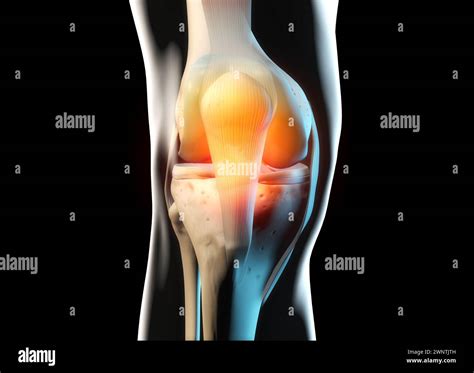

The stability of the knee is maintained by four major ligaments that hold the bones together and restrict excessive movement. These fibrous bands are crucial to the bone anatomy knee framework, preventing the knee from buckling under pressure.

• Anterior Cruciate Ligament (ACL): Located in the center of the knee, it prevents the tibia from sliding out in front of the femur.

• Posterior Cruciate Ligament (PIR): Works opposite the ACL, preventing the tibia from sliding backward under the femur.

• Medial Collateral Ligament (MCL): Runs along the inner side of the knee, protecting it from side-to-side stress.

• Lateral Collateral Ligament (LCL): Runs along the outer side of the knee, providing stability against lateral forces.